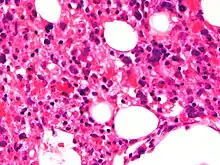

| Micrograph showing red blood cells within macrophages. H&E stain. | |

Bone marrow biopsy shows histiocytosis.[20]